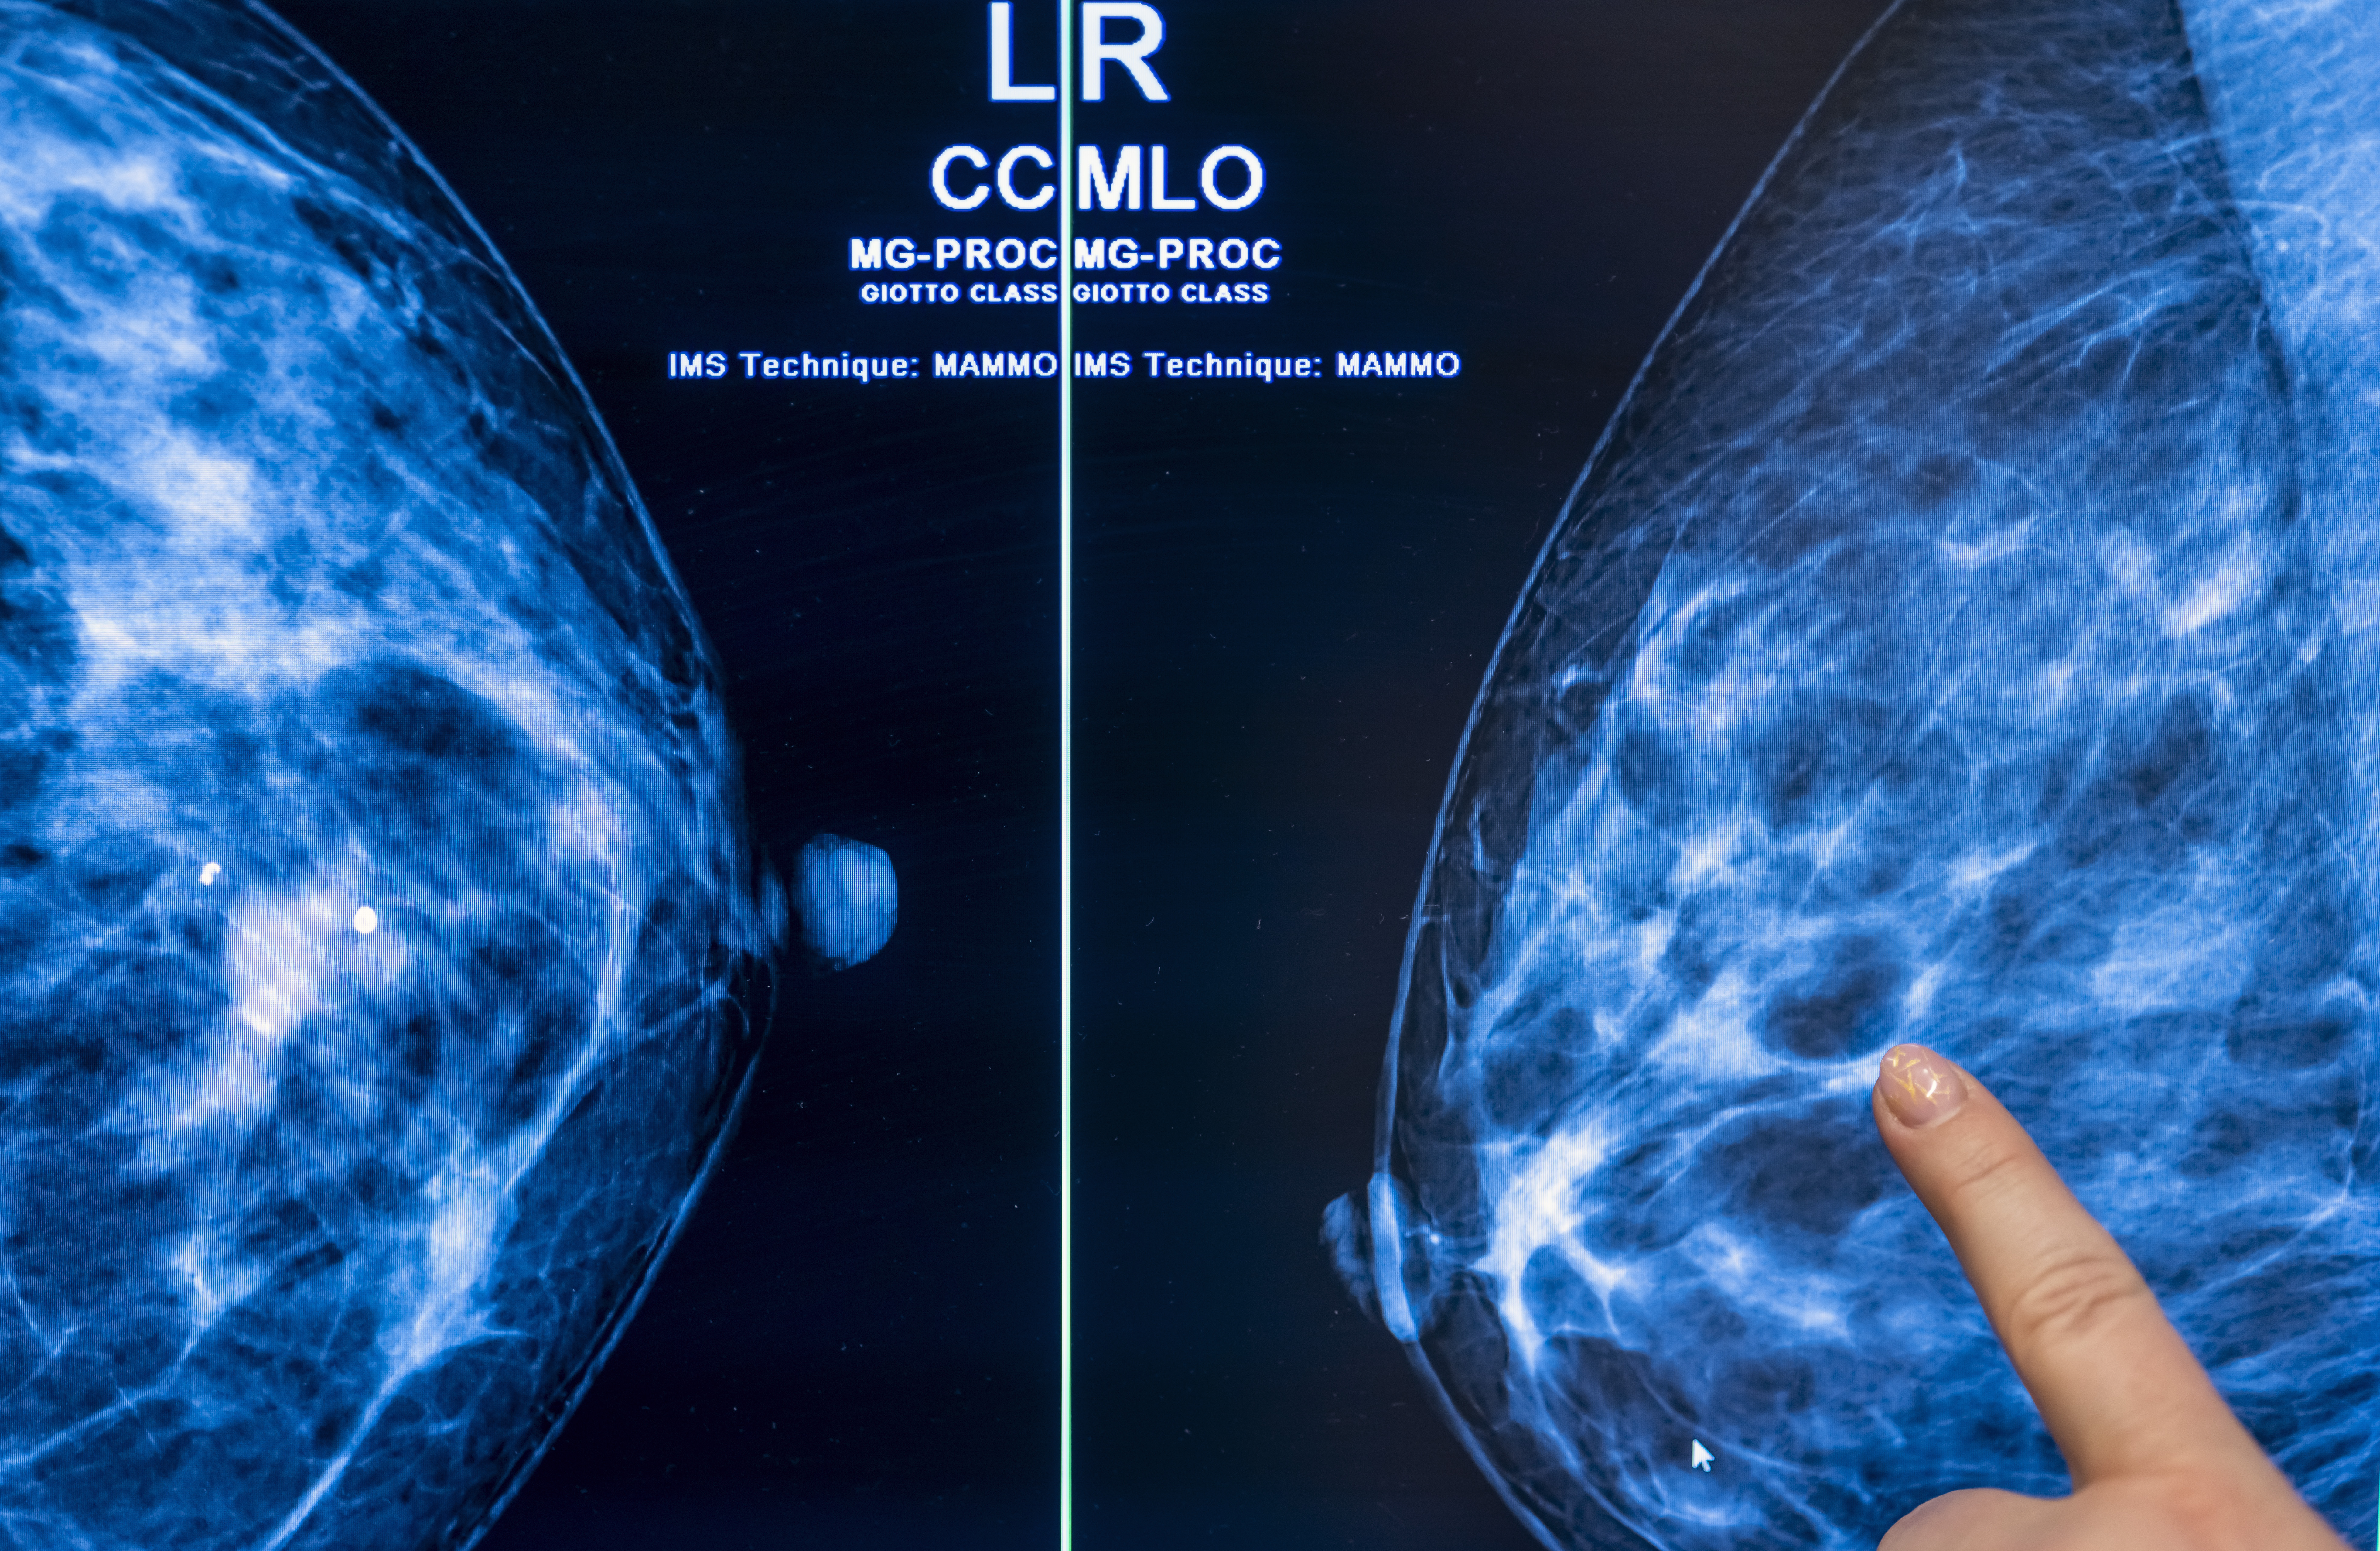

Being overweight or obese increases the risk of developing or dying breast cancer for a long time. New research suggests why: certain breast cancer tumors may feed adjacent fat cells.

Triple negative accounts for around 15% of all breast cancers. It tends to be more common in black women and women under the age of 40, and is more likely to recur than other cancers.

October is Breast Cancer Awareness Month. Here are some tips to reduce the risks for both men and women, as well as recommendations from experts regarding how often they are tested for the disease.